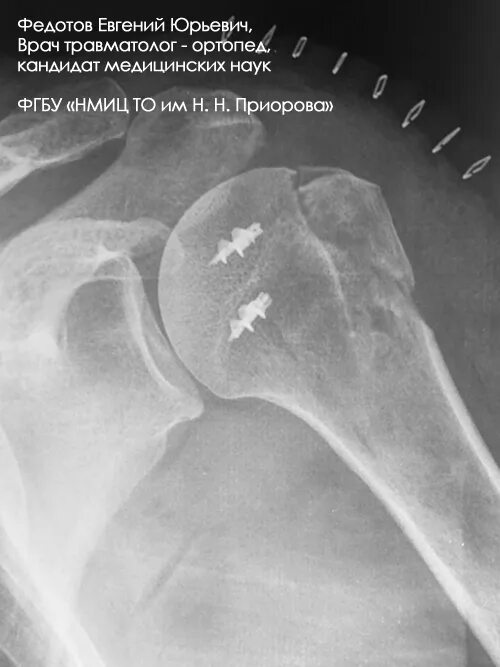

Перелом б бугорка